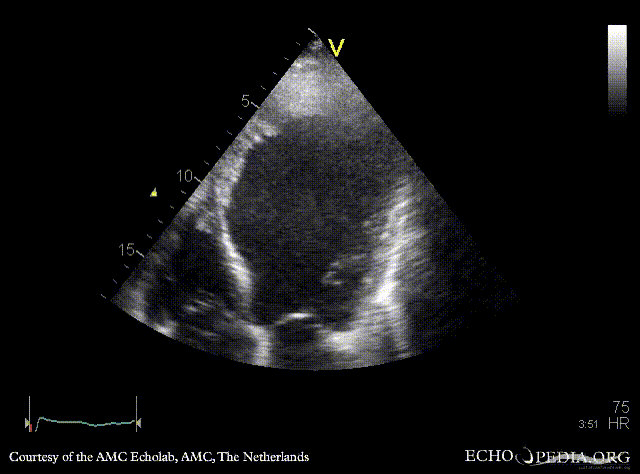

Thrombus in the apex of left ventricle

Courtesy of: AMC Echolab, AMC, The Netherlands

A4CH: dilated left ventricle, poor function, large thrombus in the apex, spontaneous echocontrast A2CH